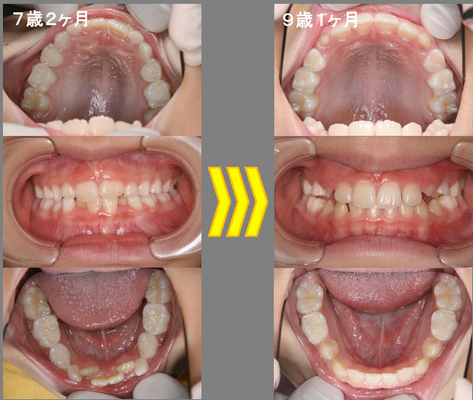

下の前歯がガタガタでキレイにしてほしいと言ってきた7歳2ヶ月の女の子。下顎の6歳臼歯がかなり内側に倒れていて、前歯部の叢生量(スペース不足)が約5mmくらいになっています。上顎はキレイに歯が並んでいるように見えますが、乳歯と乳歯の間に隙間が全くない状態であり、上顎も下顎と同様歯列が狭いと考えられます。このまま永久歯が生えそろうまで様子を見ていても歯並びが悪くなるだけです。取り外し式の床矯正装置で、上下の顎を拡大していきました。約2年で、綺麗な歯並びになりました。床矯正装置は、家の中だけで装着しました。

治療費:¥432,000 治療期間:2年